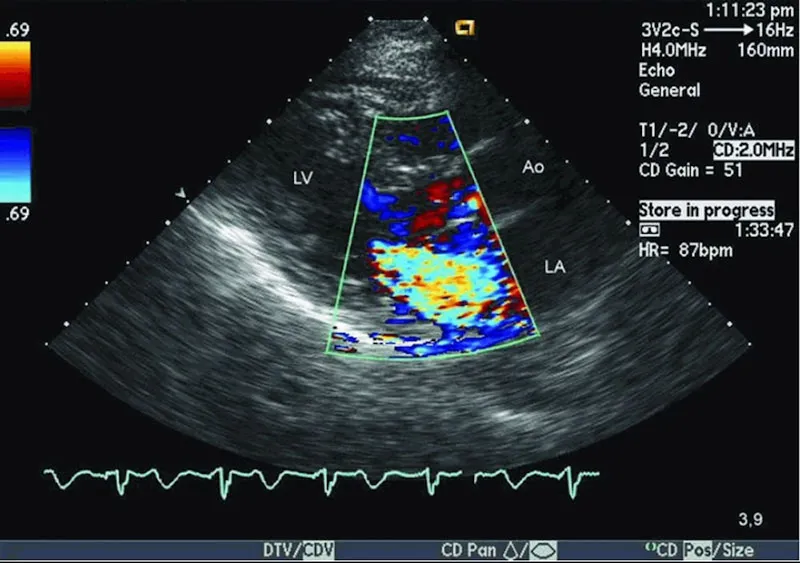

Siêu Âm Doppler

Doppler đánh giá dòng chảy máu trong mạch

Kỹ thuật đặc biệt đo tốc độ và hướng dòng máu. Quan trọng khi:

• Phát hiện tắc nghẽn động mạch, tĩnh mạch

• Đánh giá tuần hoàn thai nhi (3 tháng cuối)

• Chẩn đoán suy giảm lưu lượng máu đến cơ quan

• Kiểm tra van tim, phình mạch